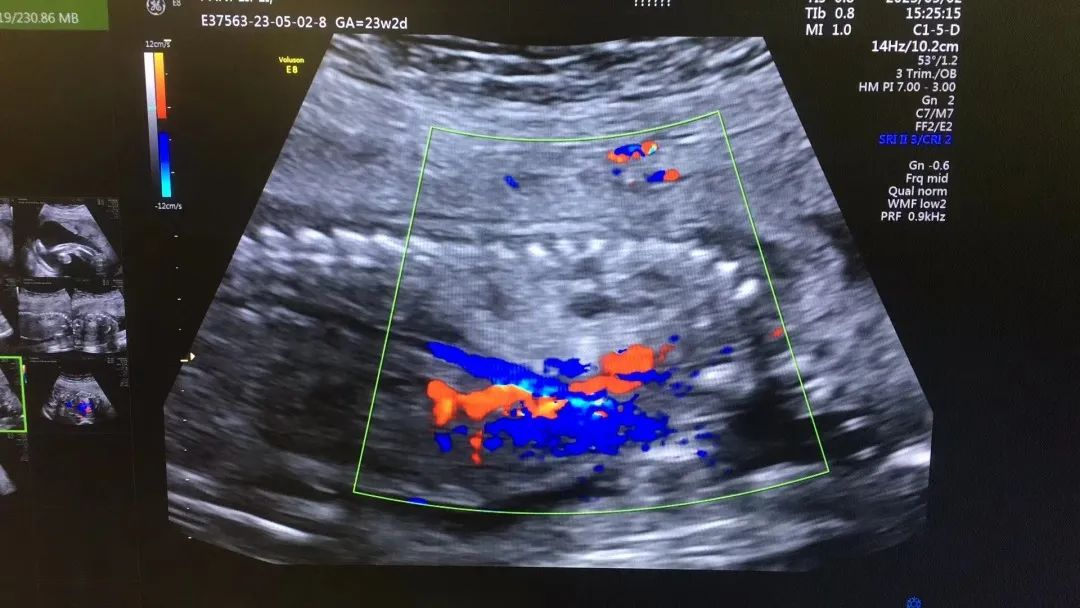

武漢的劉女士(化名),前幾個(gè)月剛懷上寶寶,全家都特別高興。懷孕23周+時(shí),劉女士在家人的陪伴下來(lái)到武漢仁愛醫(yī)院超聲科做了四維彩超檢查,當(dāng)醫(yī)生拿出檢查報(bào)告的時(shí)候,劉女士卻當(dāng)場(chǎng)傻眼了,原來(lái),在四維彩超的報(bào)告里,診斷出了胎兒右肺囊性腺瘤樣病變,她的心頓時(shí)揪了起來(lái)!

劉女士看到檢查結(jié)果后,擔(dān)心該病變會(huì)影響腹中寶寶的健康,考慮是否應(yīng)該終止妊娠。隨即,武漢仁愛醫(yī)院超聲科王娟主任為劉女士耐心地解釋:“先天性肺囊腺瘤是一種肺組織錯(cuò)構(gòu)畸形,先天性肺囊腺瘤畸形病例約70%的腫塊大小較穩(wěn)定;約20%腫塊產(chǎn)前明顯縮小或消失;僅10%腫塊是進(jìn)行性增大。單純的先天性肺囊腺瘤(CCAM)無(wú)水腫的胎兒可以密切隨訪,在28周前接受連續(xù)超聲復(fù)查,CVR<1.6,一般超聲動(dòng)態(tài)監(jiān)測(cè)2~4周監(jiān)測(cè)一次,而對(duì)于CVR≥1.6的需要在28周前每周1-2次的超聲監(jiān)測(cè),防止出現(xiàn)胎兒水腫,直到分娩。”